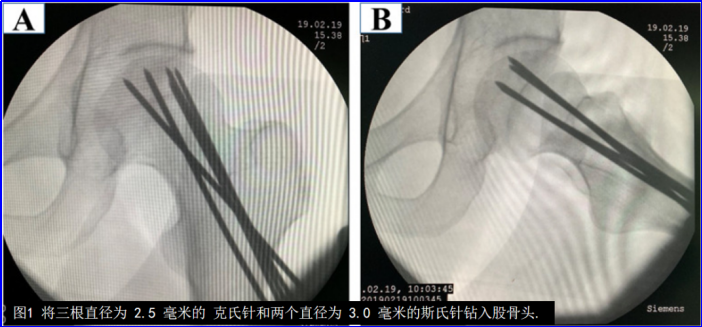

髓芯减压术(CD)有两种手术方式:一种是传统的单孔钻孔,直径为8-12毫米;另一种是多孔钻孔,直径为3-4毫米(图4)。

从生物力学角度来看,与单纯钻孔相比,多孔钻孔形成蜂窝状隧道结构,能够保留部分支撑结构,防止髓芯减压术后发生局部塌陷。多孔钻孔治疗早期股骨头坏死的成功率为68.6%-78.6%,与单纯钻孔相近。